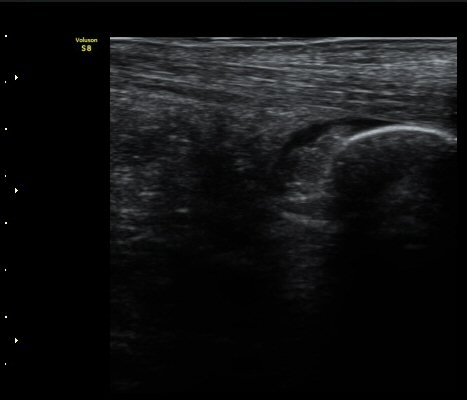

ÁÖ»ç ÈÄ ÁÖ»ç¾×¿¡ ÀÇÇØ Á¡¾×³¶³» ¼ö¾×ÀÌ Áõ°¡µÈ °ÍÀÌ È®ÀÓ µÊ(±×¸² 3).